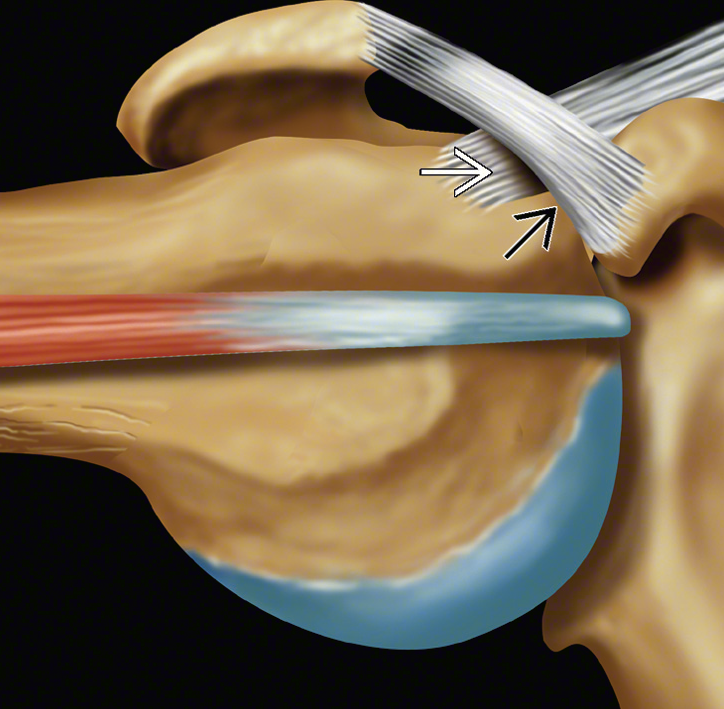

| A. Supraspinatus tendonunun korakoakromial bağ ile ilişkisi, B. Supraspinatus tendonunun sıkışmasını gösteren MR görüntüsü | |

Akromion kürek kemiğinin omuz üzerindeki kısmına verilen isimdir. Humerus başının üst kısmındadır. Kol yukarı kaldırıldığında döndürücü kılıf humerusun başı ile akromion arasında sıkışır. Bu durum ağrıya ve hareket azalmasına yol açar.

Bu sıkışma döndürücü kılıf üzerine yerleşmiş olan bursanın inflamasyonuna veya tendonlarda tendinitlere (tendonların inflamasyonu) sebep olur. Bu sıkışmalar tekrarlarsa döndürücü kılıf yırtılabilir.